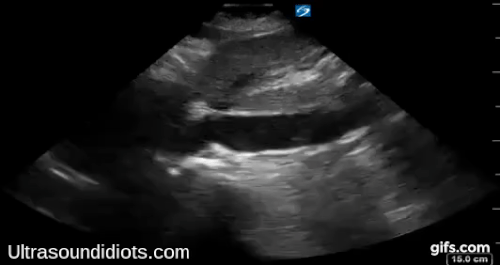

Echo Subcostal Exams